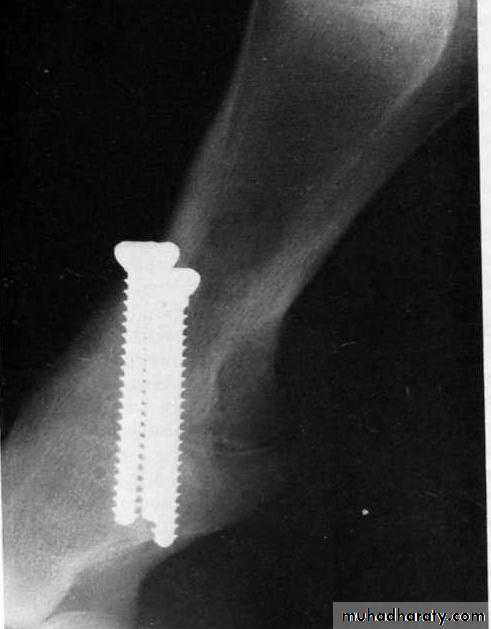

Internal fixation using plates or screws after the cartilage is removed from the joint surface. Good results have been reported with three parallel placed screws that cross the pastern joint and compress it when the screws are tightened.

A lateral radiograph 7 weeks postoperatively. Arthrodesis of the pastern joint was accomplished with three screws placed across the joint to compress it. The cartilage from the pastern joint was removed prior to screw placement. Good healing has occurred.